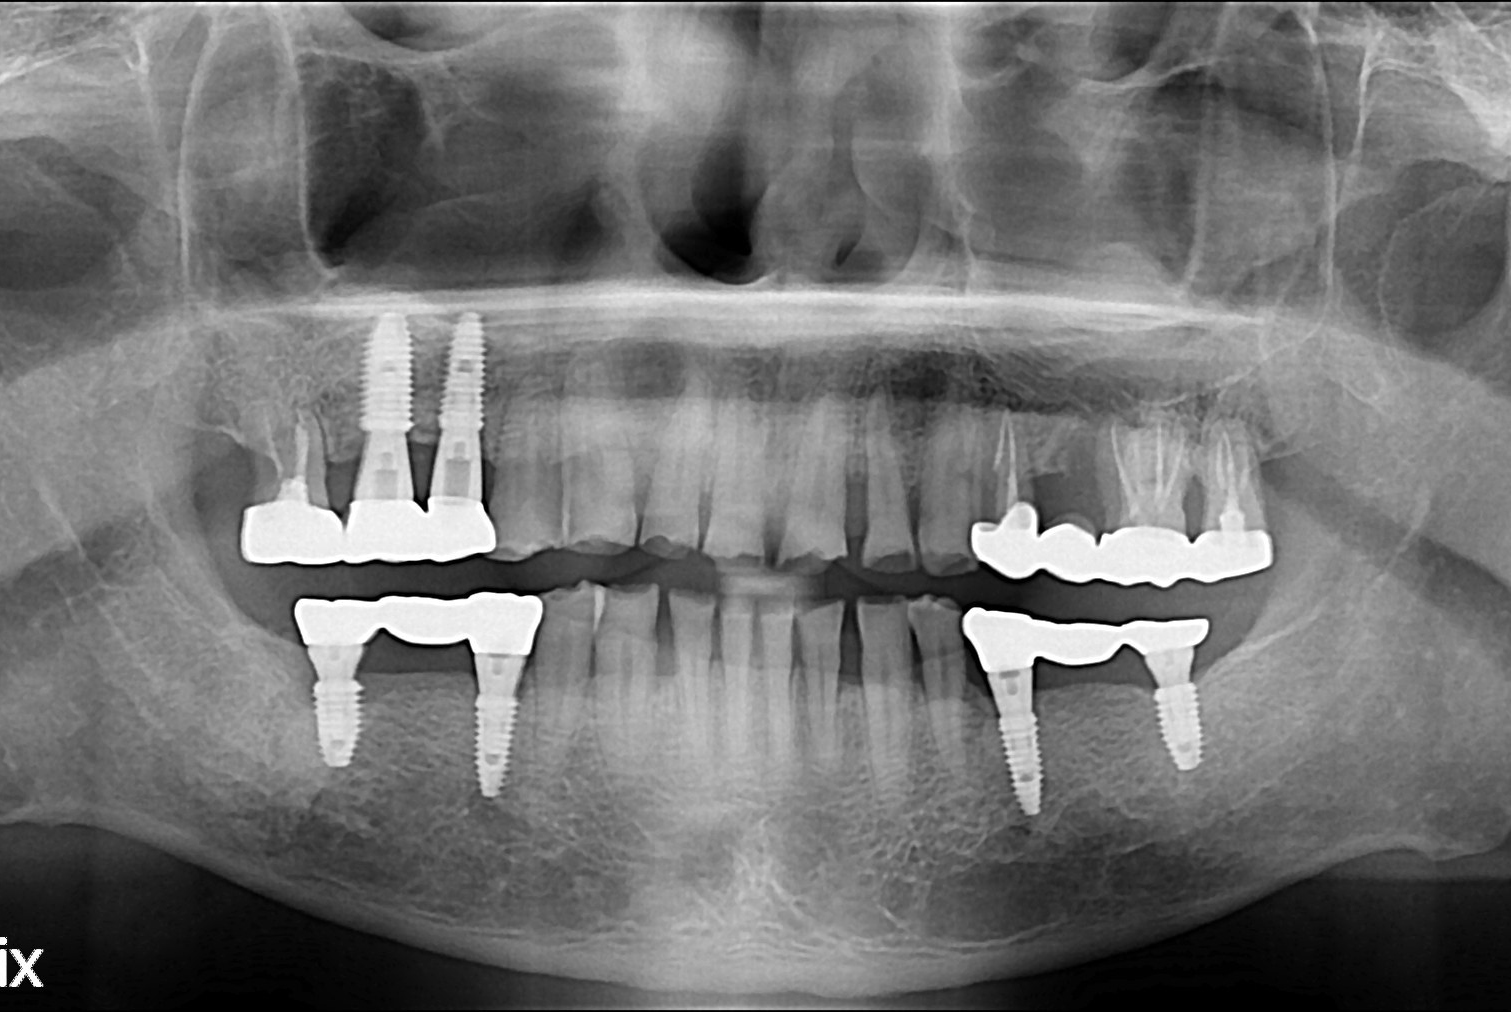

치료후 : 2018-09-21

세종치과는 많은 환자와 다양한 케이스를 바탕으로 항상 편안한 임플란트 수술을 제공하고자 노력하고,

오래동안 튼튼히 쓸 수 있는 임플란트 수술을 가장 큰 목표로 삼고 있습니다